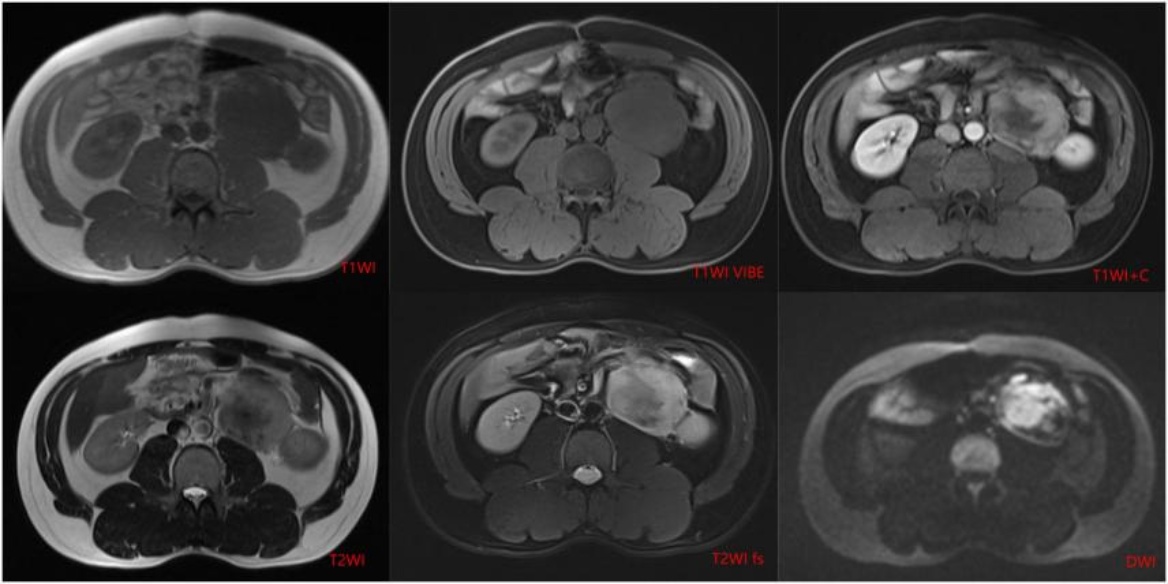

患者男,41岁。1年前气管插管全麻下行腹腔镜全大肠切除术,术后病理提示:家族性腺瘤样息肉病伴乙状结肠中分化管状腺癌。术后行“奥沙利铂 + 卡培他滨”化疗6次,化疗期间肿瘤指标正常。1年后复查全腹CT所见:左肾前下方及肠系膜内亦见多发肿块,较大者位于左肾前下方,大小约2.7 cm × 2.3 cm × 3.6 cm (左右径 × 前后径 × 上下径),边界光整,等密度;动脉期轻度强化,内见血管穿行;静脉期及延迟期呈渐进、延迟不均质强化,内见低密度区,肿块与左侧输尿管上段分界不清,以上肾盂积液轻度扩张,再经3个月后,复查全腹CT (图1图2)提示腹腔肿块明显增大,病灶大小约6.6 cm × 5.7 cm × 8.7 cm (左右径 × 前后径 × 上下径)。随后完善腹部MR (图3),所见:左肾前下方见及肠系膜内亦见多发长T1不均匀长T2信号影,弥散未见明显受限,增强扫描呈渐进性不均匀强化,内见无强化坏死区,肿块局部向后压迫左侧输尿管上段并分界不清,以上输尿管及肾盂轻度积液扩张。综合CT及MR影像诊断:转移瘤可能性大。但患者体重稳定增加,复查肿瘤指标仍未见异常,影像诊断与临床不符。

Figure 3. Multiparametric magnetic resonance imaging

3. 多参数磁共振成像

磁共振成像(Magnetic Resonance Imaging, MRI):MRI是评估硬纤维瘤病的首选影像学方法,具有多参数、多平面成像能力及优异的软组织分辨率。典型MRI表现为:T1加权像(T1-weighted imaging, T1WI)呈等或稍低信号(与肌肉相比);T2加权像(T2-weighted imaging, T2WI)信号多变,取决于肿瘤内细胞成分、胶原纤维含量及黏液变性程度:细胞丰富、活性高的肿瘤通常呈高信号,而胶原成分多、分化成熟的肿瘤则呈低信号,部分可呈混杂信号。增强T1WI (脂肪抑制序列)呈不均匀渐进性强化,与CT增强表现类似。弥散加权成像(Diffusion-weighted imaging, DWI)序列上,肿瘤通常呈扩散受限,ADC值降低。MRI功能成像如动态对比增强MRI (Dynamic contrast-enhanced magnetic resonance imaging, DCE-MRI)和DWI有助于评估肿瘤的血流灌注和细胞密度,预测肿瘤活性及治疗反应。部分研究提示,T2WI高信号比例(如>50%)可能与肿瘤生长速度快、进展风险高相关,可作为风险分层的影像学指标[11]。影像学随访方面,通常建议每3~6个月进行一次MRI或CT检查,评估肿瘤大小(最长径及体积)、信号特征(如T2WI信号变化)及与周围结构的关系,以监测肿瘤。

在上述报道病例中,患者为家族性腺瘤样息肉病并癌变患者,后CT复查腹腔内出现占位,需要与结肠癌腹腔内淋巴结转移瘤相鉴别。CT对于两者的鉴别诊断相对困难,磁共振成像则有较高敏感度。病变的T2WI图像在病灶内部呈现不均质的低信号,在相对应的DWI上呈现高信号,可能与病灶内含有纤维成分,这一影像表现与病理结果中纤维母细胞及肌纤维母细胞增生,平行排列,交错排列,部分区域胶原化相一致。而淋巴结转移瘤随着病灶增大,病灶内部往往会出现缺血坏死的表现,在T2WI图像上会呈现高信号,对应的表观扩散系数(Apparent diffusion coefficient, ADC)则会呈现低信号。这点提示医生,对于有家族性腺瘤样息肉并癌变行肠道切除术后的患者新发现腹腔包块时,我们需要将硬纤维瘤纳入考虑范围,帮助临床采取正确的治疗方法,避免过度切除以及不必要的治疗。